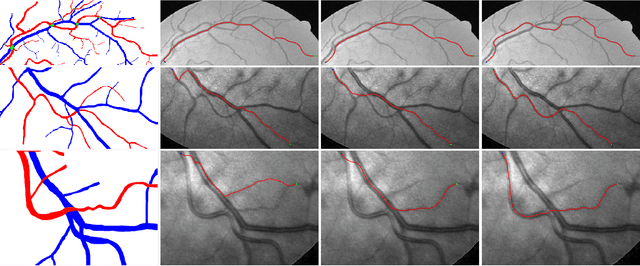

In this paper, we propose a new minimal path model for minimally interactive retinal vessel centerline extraction. The main contribution lies at the construction of a novel coherence-penalized Riemannian metric in a lifted space, dependently of the local geometry of tubularity and an external scalar-valued reference feature map. The globally minimizing curves associated to the proposed metric favour to pass through a set of retinal vessel segments with low variations of the feature map, thus can avoid the short branches combination problem and shortcut problem, commonly suffered by the existing minimal path models in the application of retinal imaging. We validate our model on a series of retinal vessel patches obtained from the DRIVE and IOSTAR datasets, showing that our model indeed get promising results.